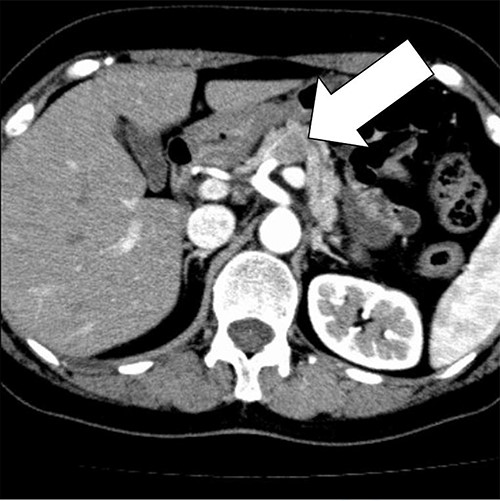

A biopsy of the pancreatic mass under endoscopic ultrasound fine-needle aspiration revealed atypical foci of cells with multinucleated giant cells suggesting ACP. Distal pancreatectomy with lymph nodes dissection was carried out based on the diagnosis of anaplastic carcinoma of the pancreatic body. The resected body and tail of the pancreas had a nodular tumor measuring 30 mm in diameter, and cut surface revealed the tumor was surrounded by fibro adipose capsule-like tissue, and the central area was composed of follicular structures that contain brown red-colored fluid (Fig. 3).

The resected body and tail of the pancreas had a nodular tumor measuring 30 mm in diameter, and cut surface revealed the tumor was surrounded by fibro adipose capsule-like tissue, and the central area was composed of follicular structures that contain brown red-colored fluid.